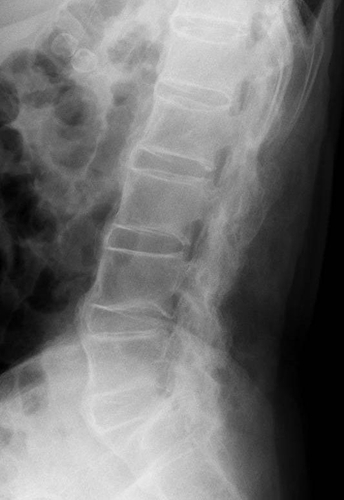

希少難病である強直性脊椎炎は、病変部位では靭帯と骨との付着部位に炎症・骨化が起こり(図1)、疼痛、運動制限等がみられ、重症例では、体軸関節の強直をきたして日常生活能力の著しい低下をもたらします。FPP003は幅広い炎症性疾患に関与するタンパク質IL-17Aに対する抗体を誘導するペプチド治療ワクチンであり、強直性脊椎炎に代表される体軸性脊椎関節炎の新規治療選択肢となることが期待されます。

仙腸関節炎や脊椎炎による腰背部痛や臀部痛が初発症状となることが多いことが知られており、疼痛が運動により軽快し、安静や就寝により増悪する炎症性腰背部痛が特徴です。アキレス腱の付着部である踵部を始め、身体各所の靱帯付着部(関節周辺の骨性突出部など)の炎症徴候(疼痛、腫脹)がしばしば見られ、時に股、膝、肩など四肢の大関節の疼痛や運動制限も生じます。IL-17Aは、関節炎に特徴的な付着部炎において重要な役割を果たしていると考えられています(図2)。抗IL-17A抗体医薬品は、既存治療で効果不十分な尋常性乾癬、関節症性乾癬、膿疱性乾癬に対し治療効果が認められており、本邦でも強直性脊椎炎、X線所見を伴わない体軸性脊椎関節炎に対しても複数の製剤が承認されています。

希少難病である強直性脊椎炎は、腰椎などの体軸関節で靭帯と骨との付着部位に炎症・骨化が起こり、疼痛、運動制限等がみられ、重症例では、体軸関節の強直をきたして日常生活能力の著しい低下をもたらします。FPP003は幅広い炎症性疾患に関与するタンパク質IL-17Aに対する抗体を誘導するペプチド治療ワクチンであり、強直性脊椎炎に代表される体軸性脊椎関節炎の新規治療選択肢となることが期待されます。